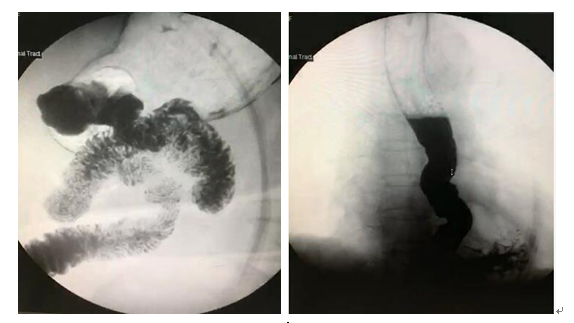

俗话说:人是铁,饭是钢,一顿不吃饿得慌。但对于今年已经92岁的张爷爷(化名)来说,最近“好好吃饭”已然变成了奢望。所幸在燕达医院消化内科的治疗下,短短半个小时就置入好了食管支架,患者及家属对治疗效果都很满意。